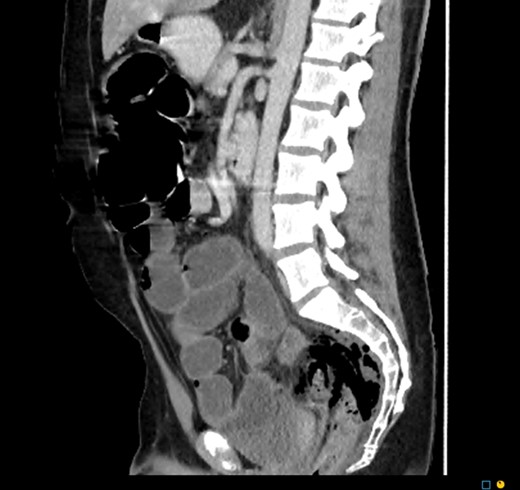

In the regional hospital, the patient had progressive peritonitis and vomiting. He was tachycardic and febrile (Temp 38.5°C). His initial work up demonstrated urea 11.9 mmol/l, creatinine 121 umol/l, C-reactive protein 201 mg/l, white cell count 30.7 × 109/l and haemoglobin 112 g/l. An urgent CT abdomen and pelvis demonstrated a large amount of free gas in the perirectal space consistent with a rectal perforation (Figs 1–3). The rectum itself was thick-walled and oedematous, as well as the sigmoid colon. He was transferred to the referral Tertiary hospital where an urgent laparotomy was performed.

CT sagittal. Large amount of perirectal free gas consistent with rectal perforation. The rectum is thick-walled and oedematous suggestive of ischaemia.